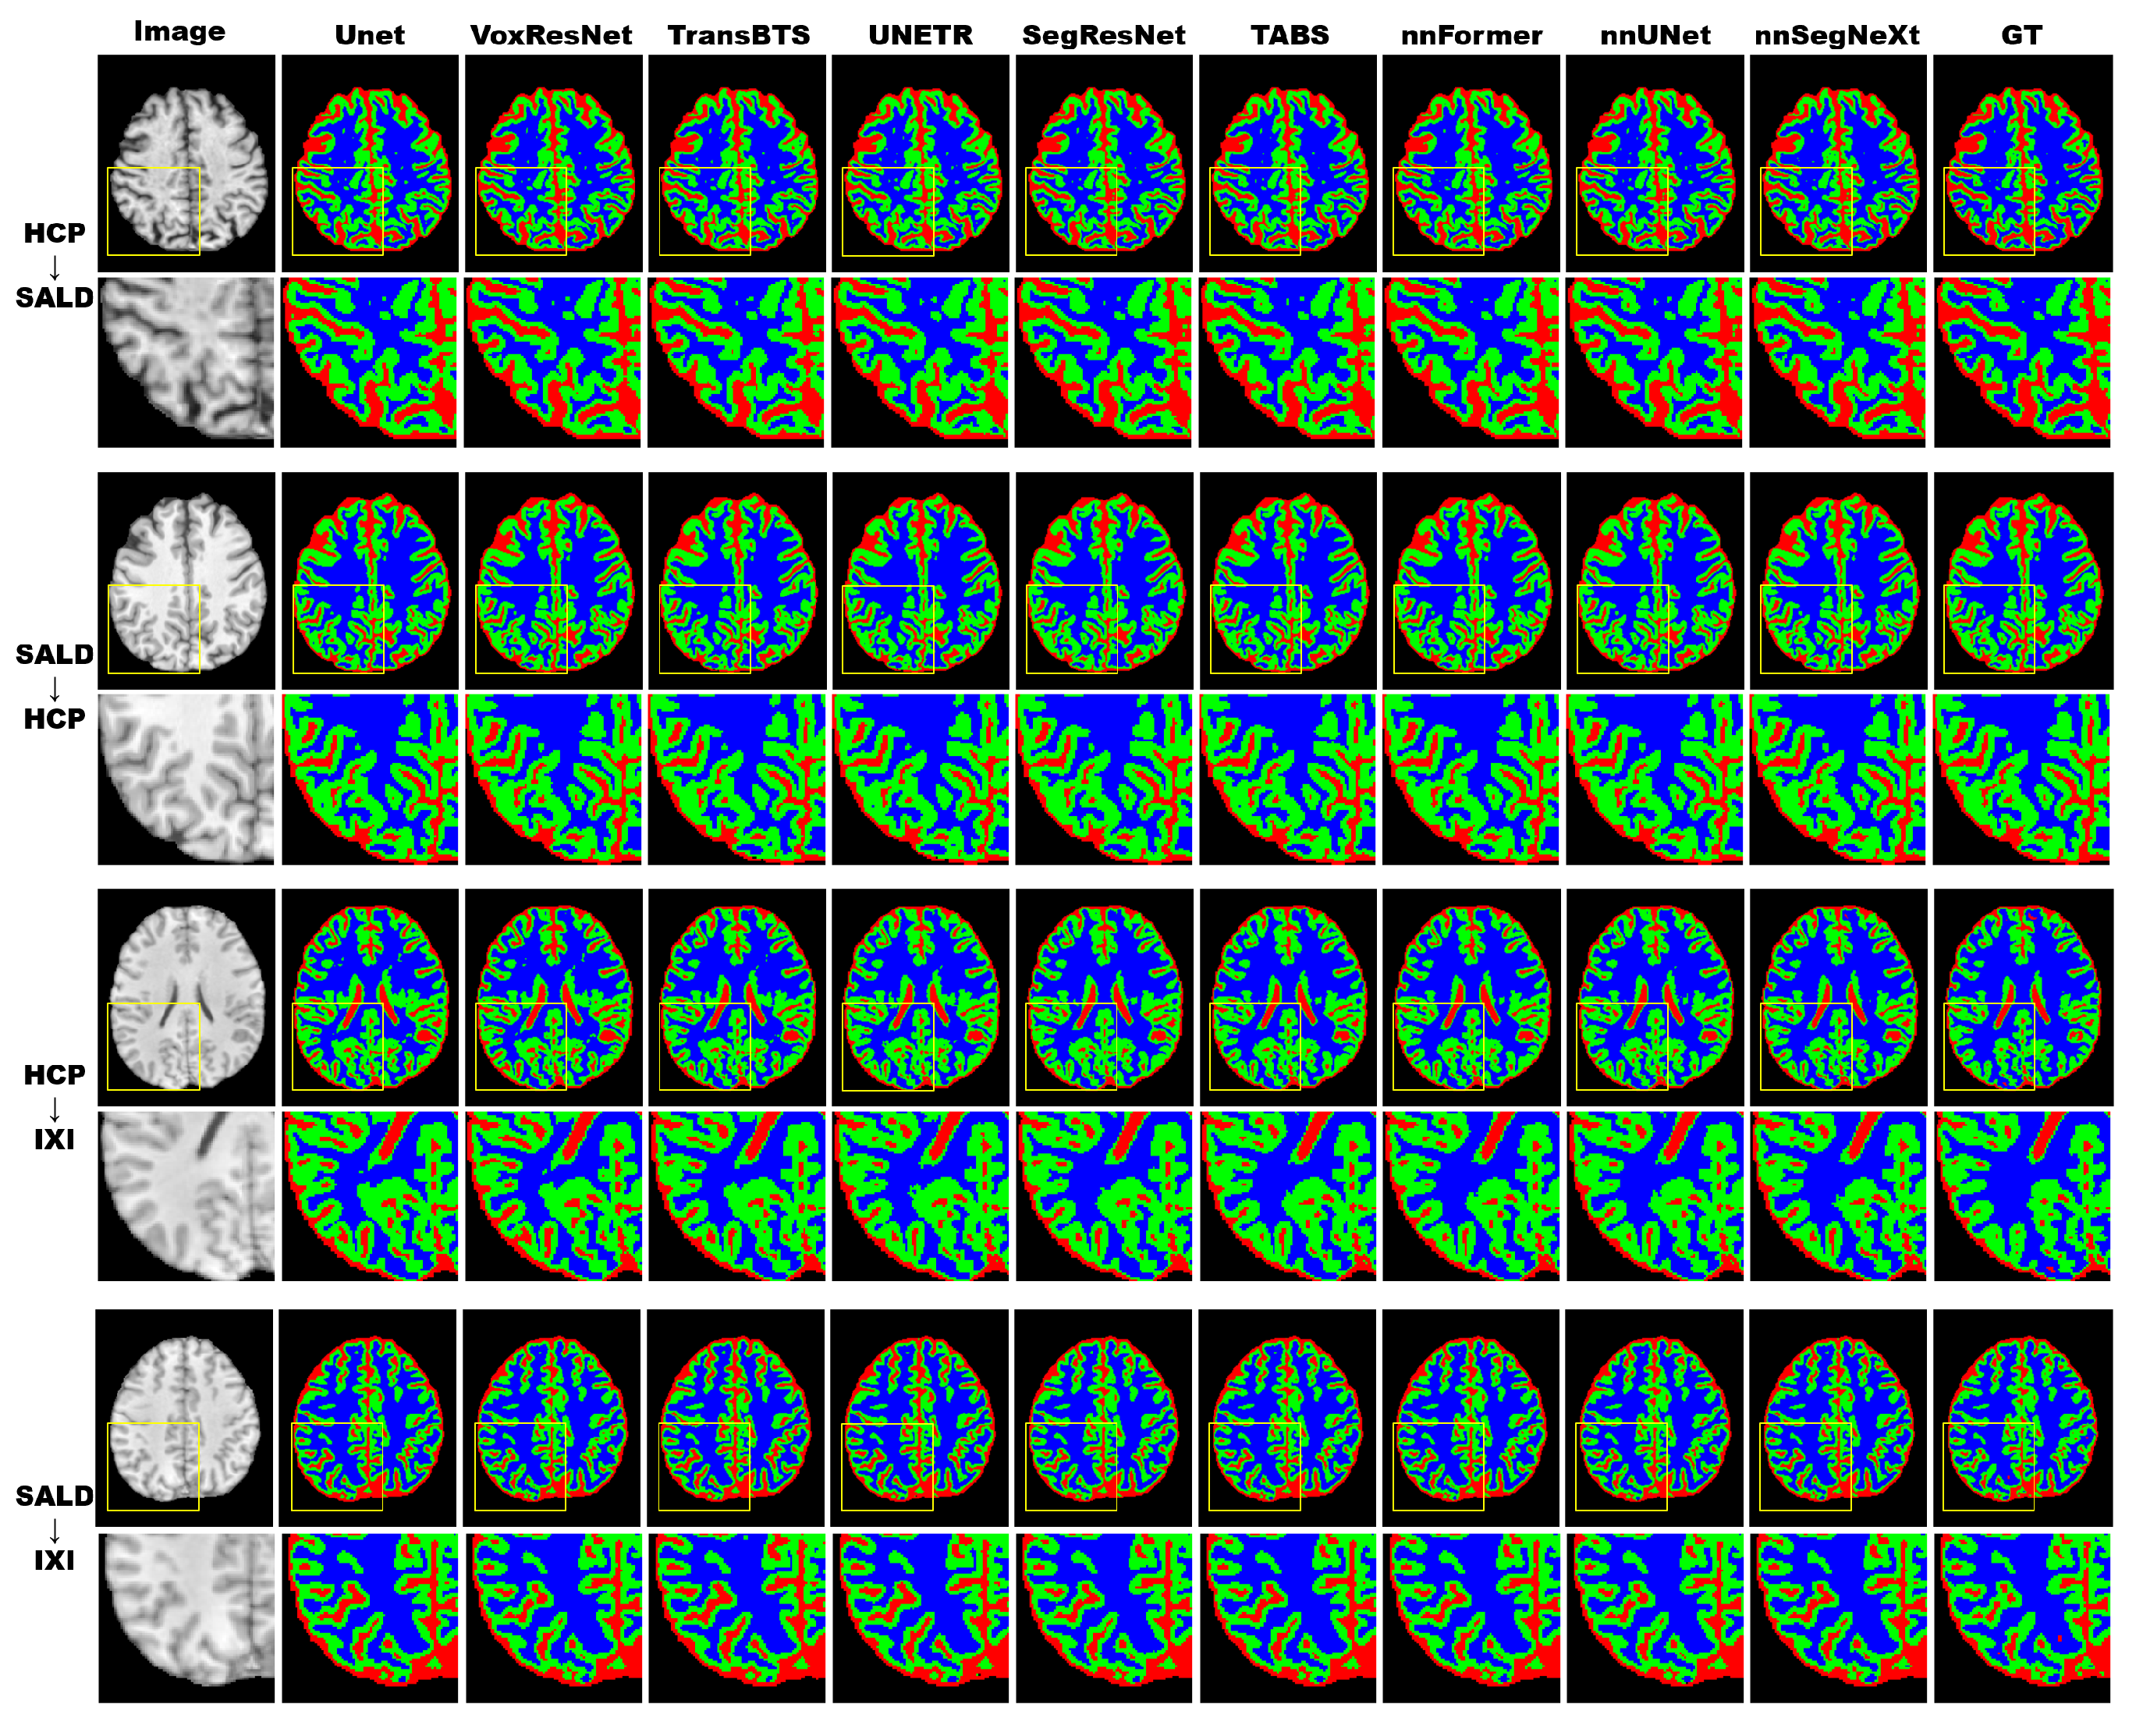

3.4.2. Model Generality